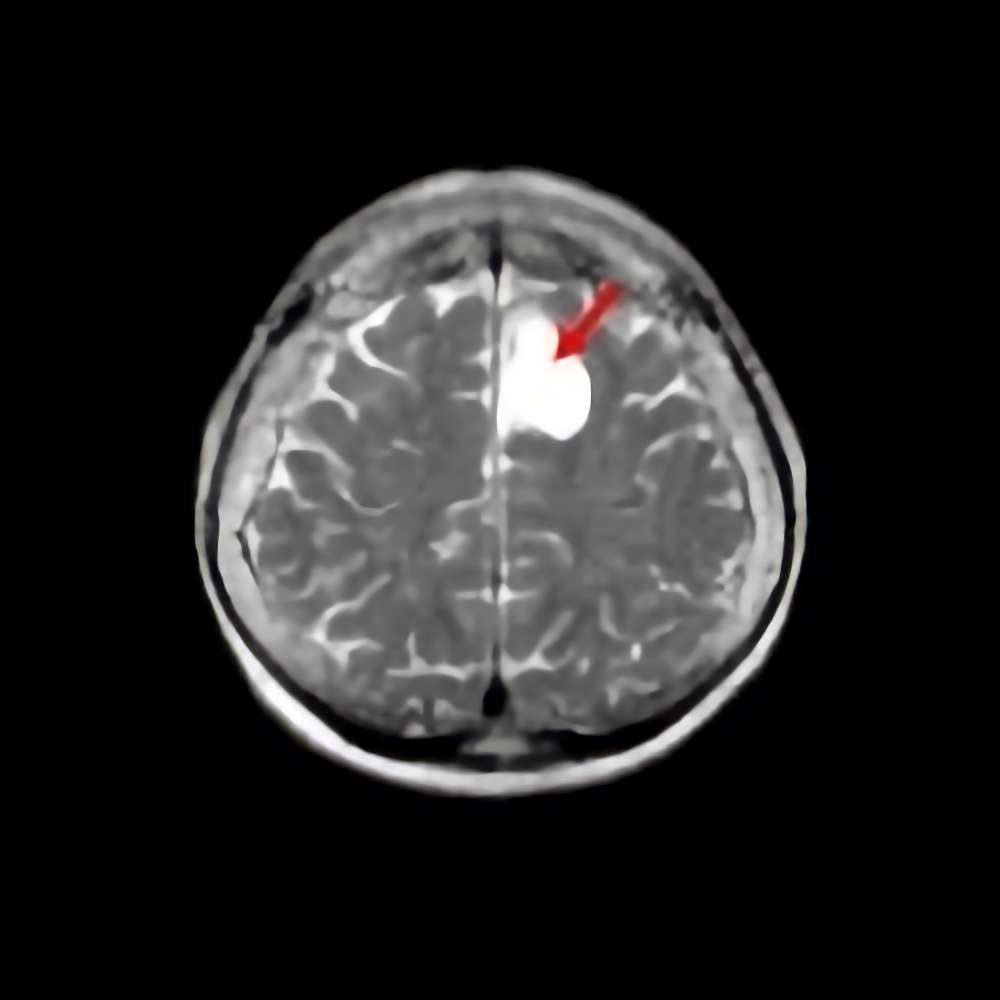

30代

海綿状血管腫

No.’15_49 手術前1

No.’15_49 摘出 前

No.’15_49 摘出 後